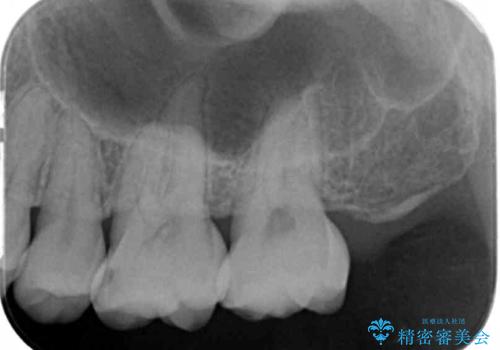

定期的にX線写真を撮影しチェックすることで、外から見てわかるプラークコントロールだけでなく虫歯を初期段階で発見し対策することができます。

歯ぎしりの癖があることから強度に優れるゴールドインレーにて修復を行いました。